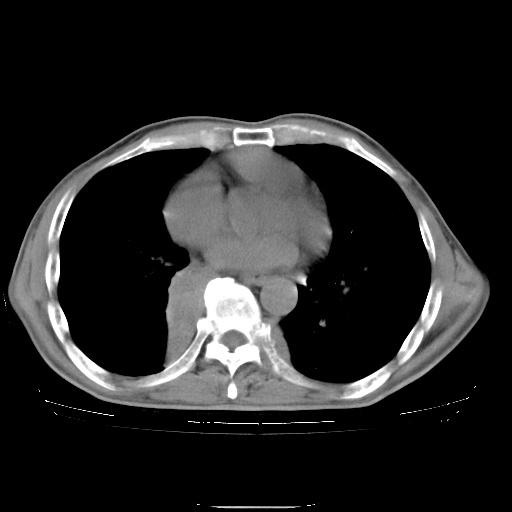

男性患者,63岁。右侧胸背部疼痛2月,加重一周。

考虑:右肺中央型肺癌并右肺下叶不张;两肺尖继发性肺结核。

还有纵隔多处肿大淋巴结及肋骨的改变、两肺多发结节灶。

右下中央型肺癌伴肺内纵膈转移。

右下肺中心型肺癌并肺不张

纵隔淋巴结转移

右肺下叶支气管狭窄闭塞,右下肺不张,气管前间隙淋巴结肿大,两上肺散在分部粟粒灶,沿肺血管支气管束分部,血管支气管束走形较为光滑。考虑右肺中心型肺癌合并肺不张,纵隔淋巴结转移,两上肺癌性淋巴管炎

右肺下叶中心性肺癌并纵隔淋巴结转移,左侧肋骨转移。双肺上叶继发性结核表现。